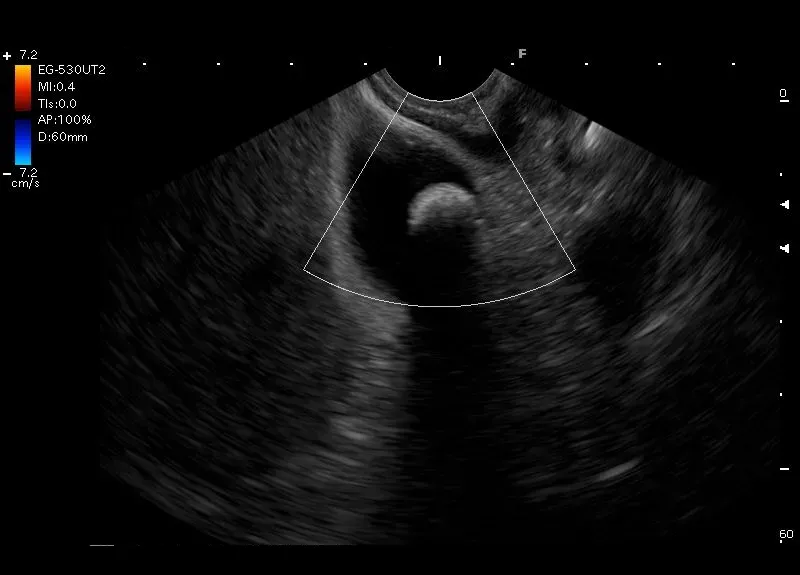

Hiperechogeniczna zmiana z cieniem akustycznym, bez przepływu naczyniowego w opcji Doppler, widoczna w świetle obkurczonego pęcherzyka żółciowego - złóg w pęcherzyku żółciowym

Hiperechogeniczna zmiana z cieniem akustycznym, bez przepływu naczyniowego w opcji Doppler, widoczna w świetle obkurczonego pęcherzyka żółciowego - złóg w pęcherzyku żółciowym